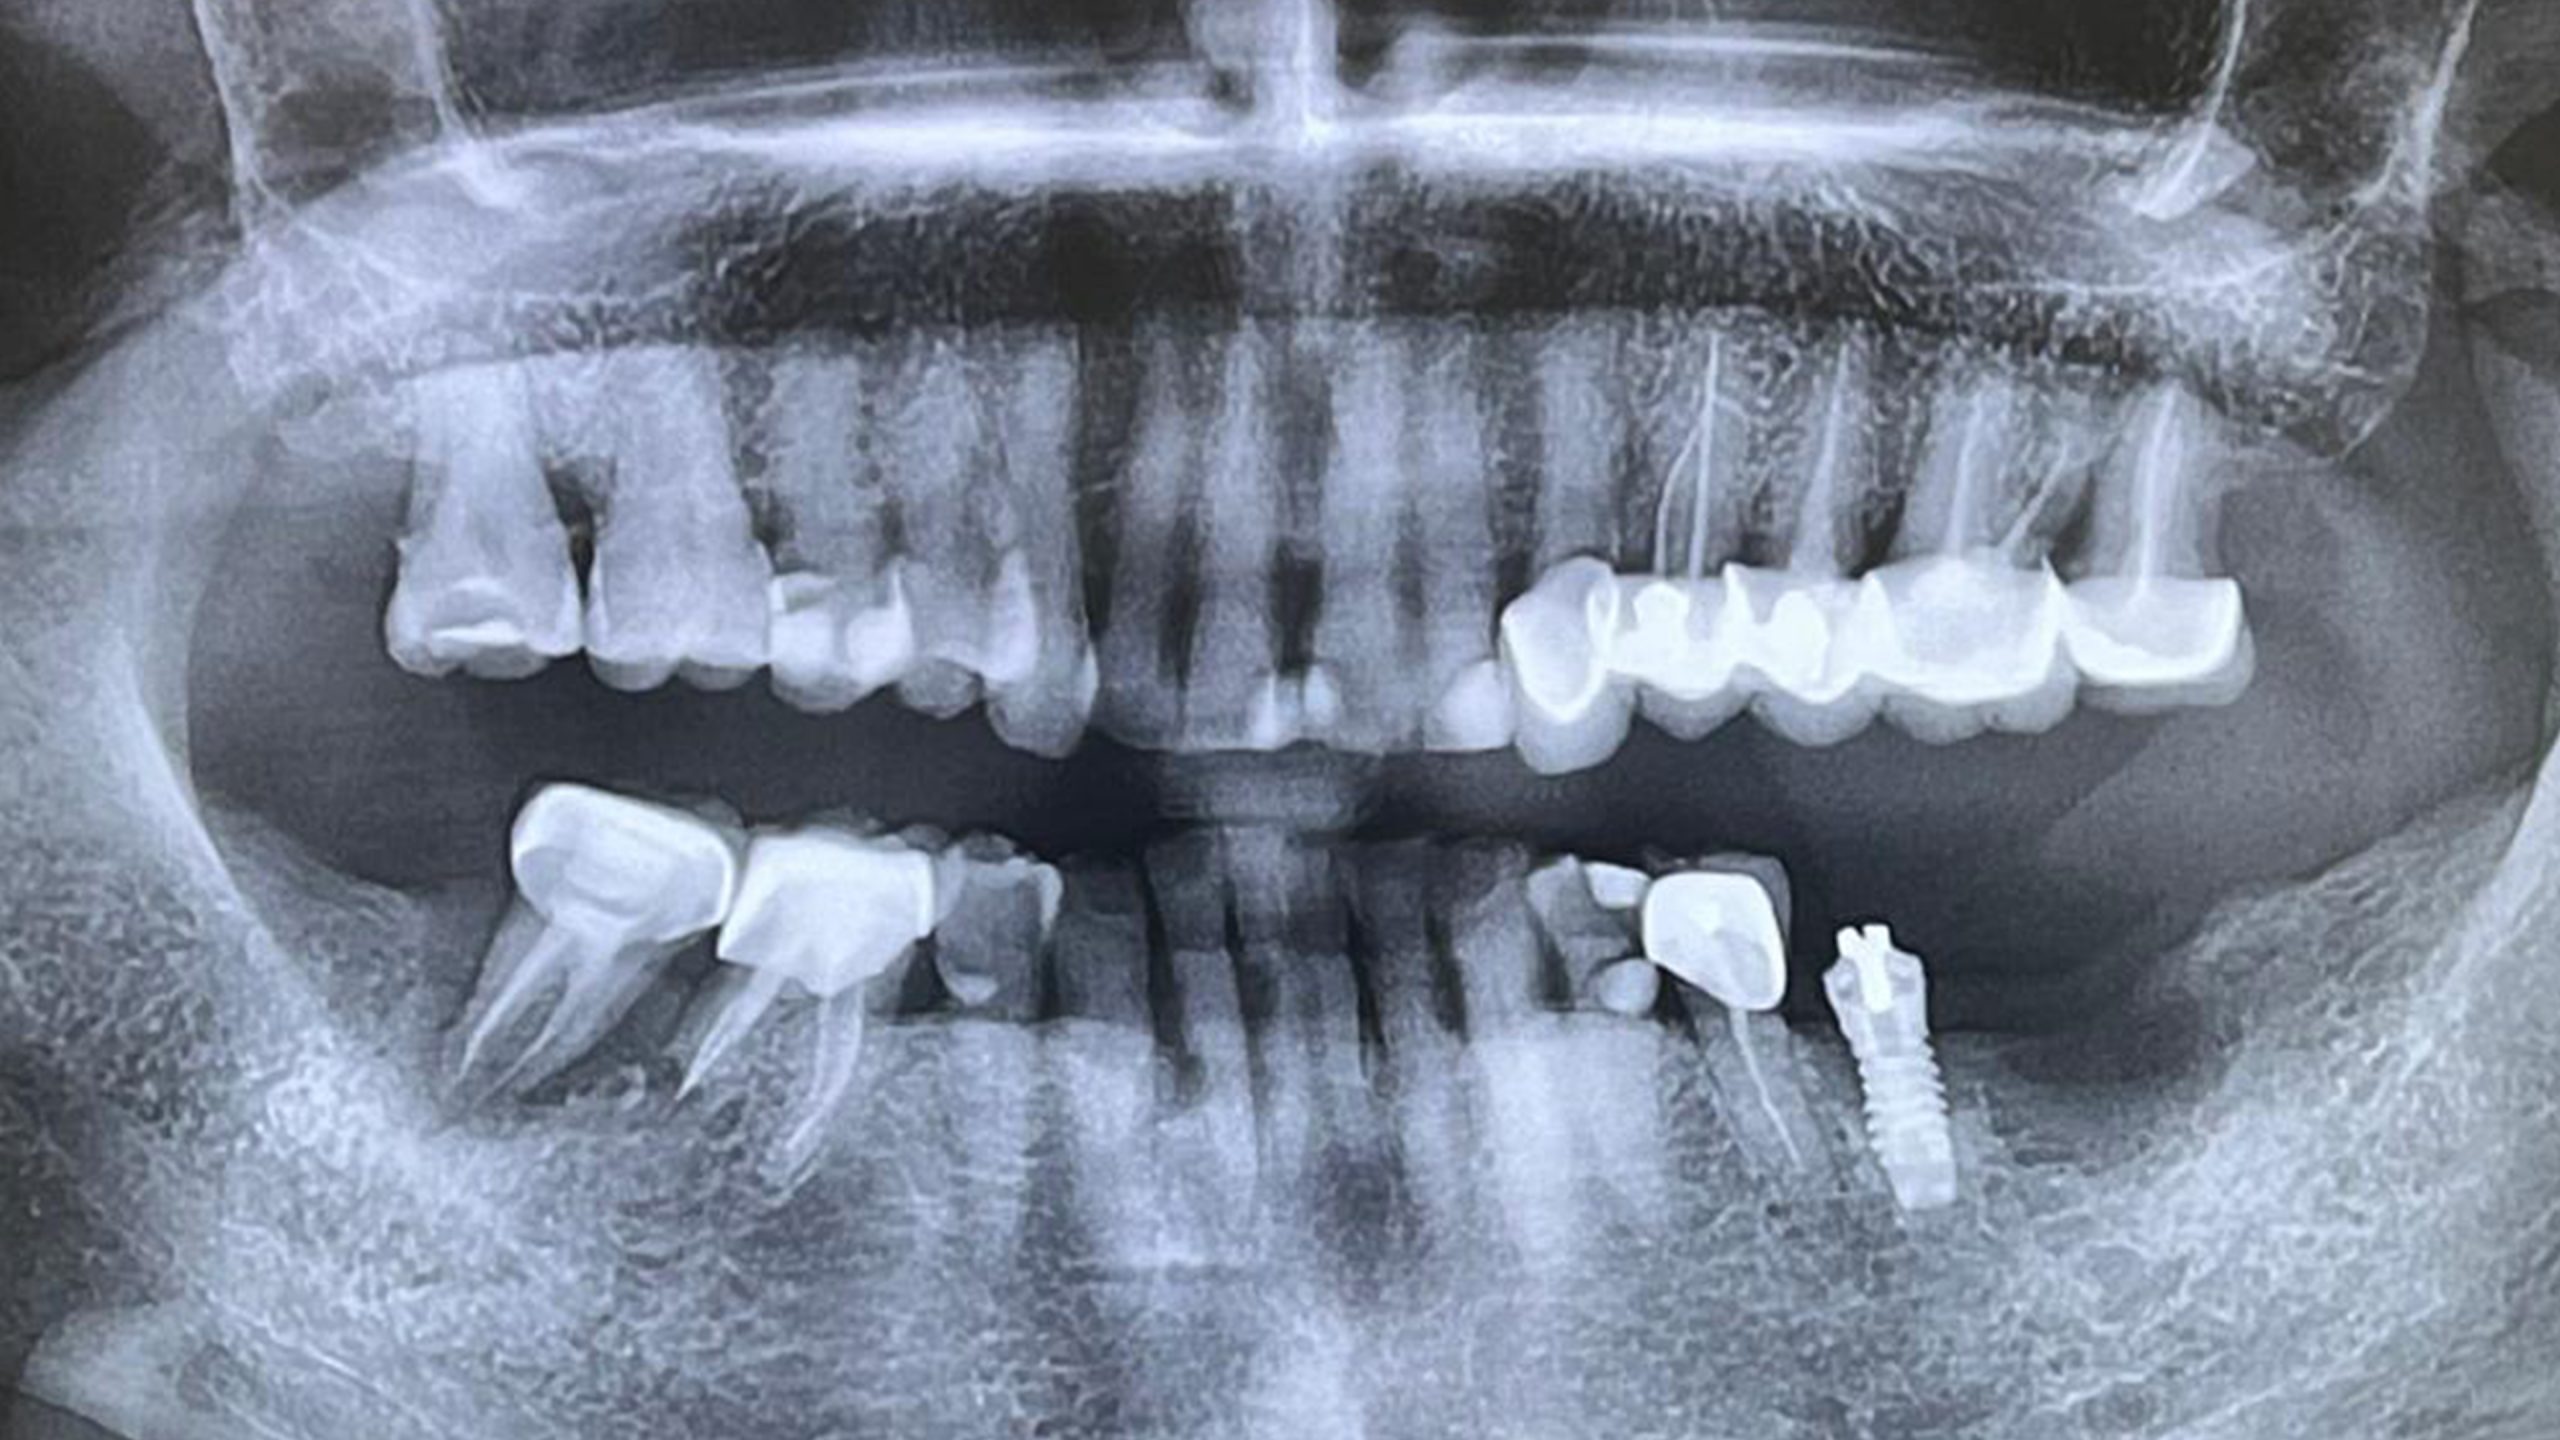

une chirurgie en direct commentée par le Dr Gérard Scortecci, réalisée dans le secteur 3 mandibulaire gauche, en 37.

La patiente présentait une perte significative du support osseux, datant de plus de 15 ans, et ayant conduit à une cavitation importante de la zone concernée.